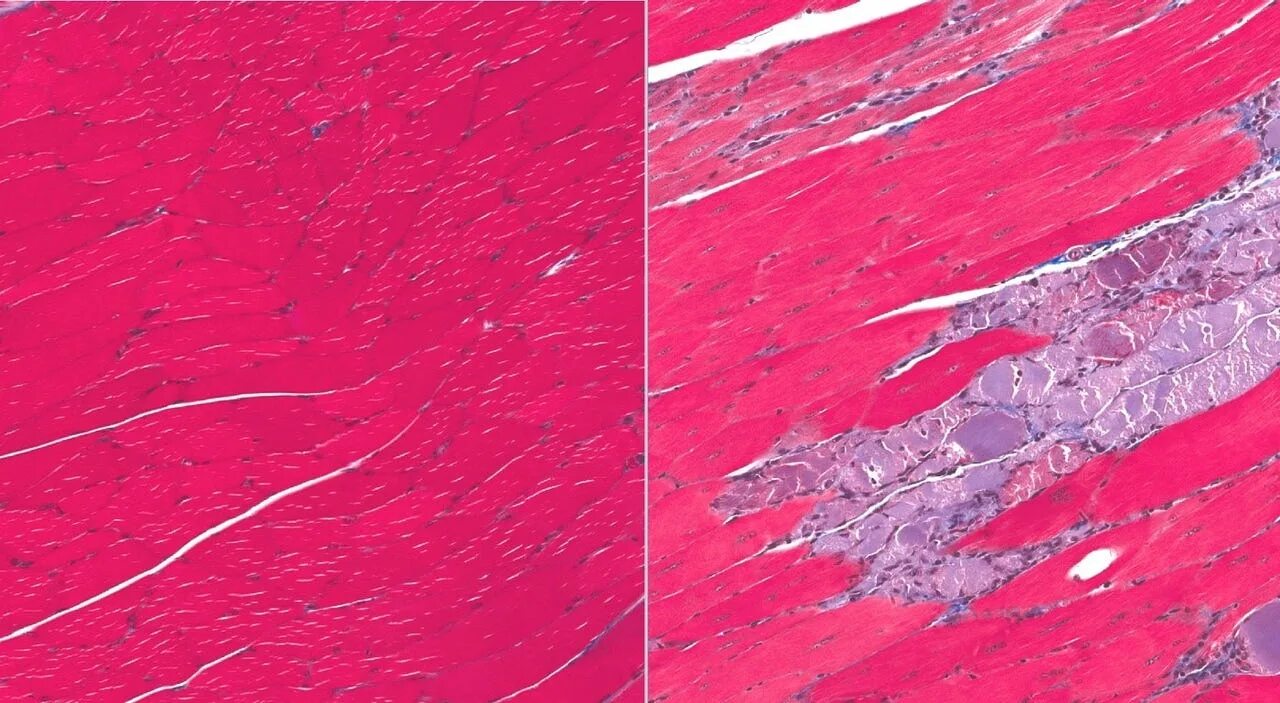

Собака атрофия мышц